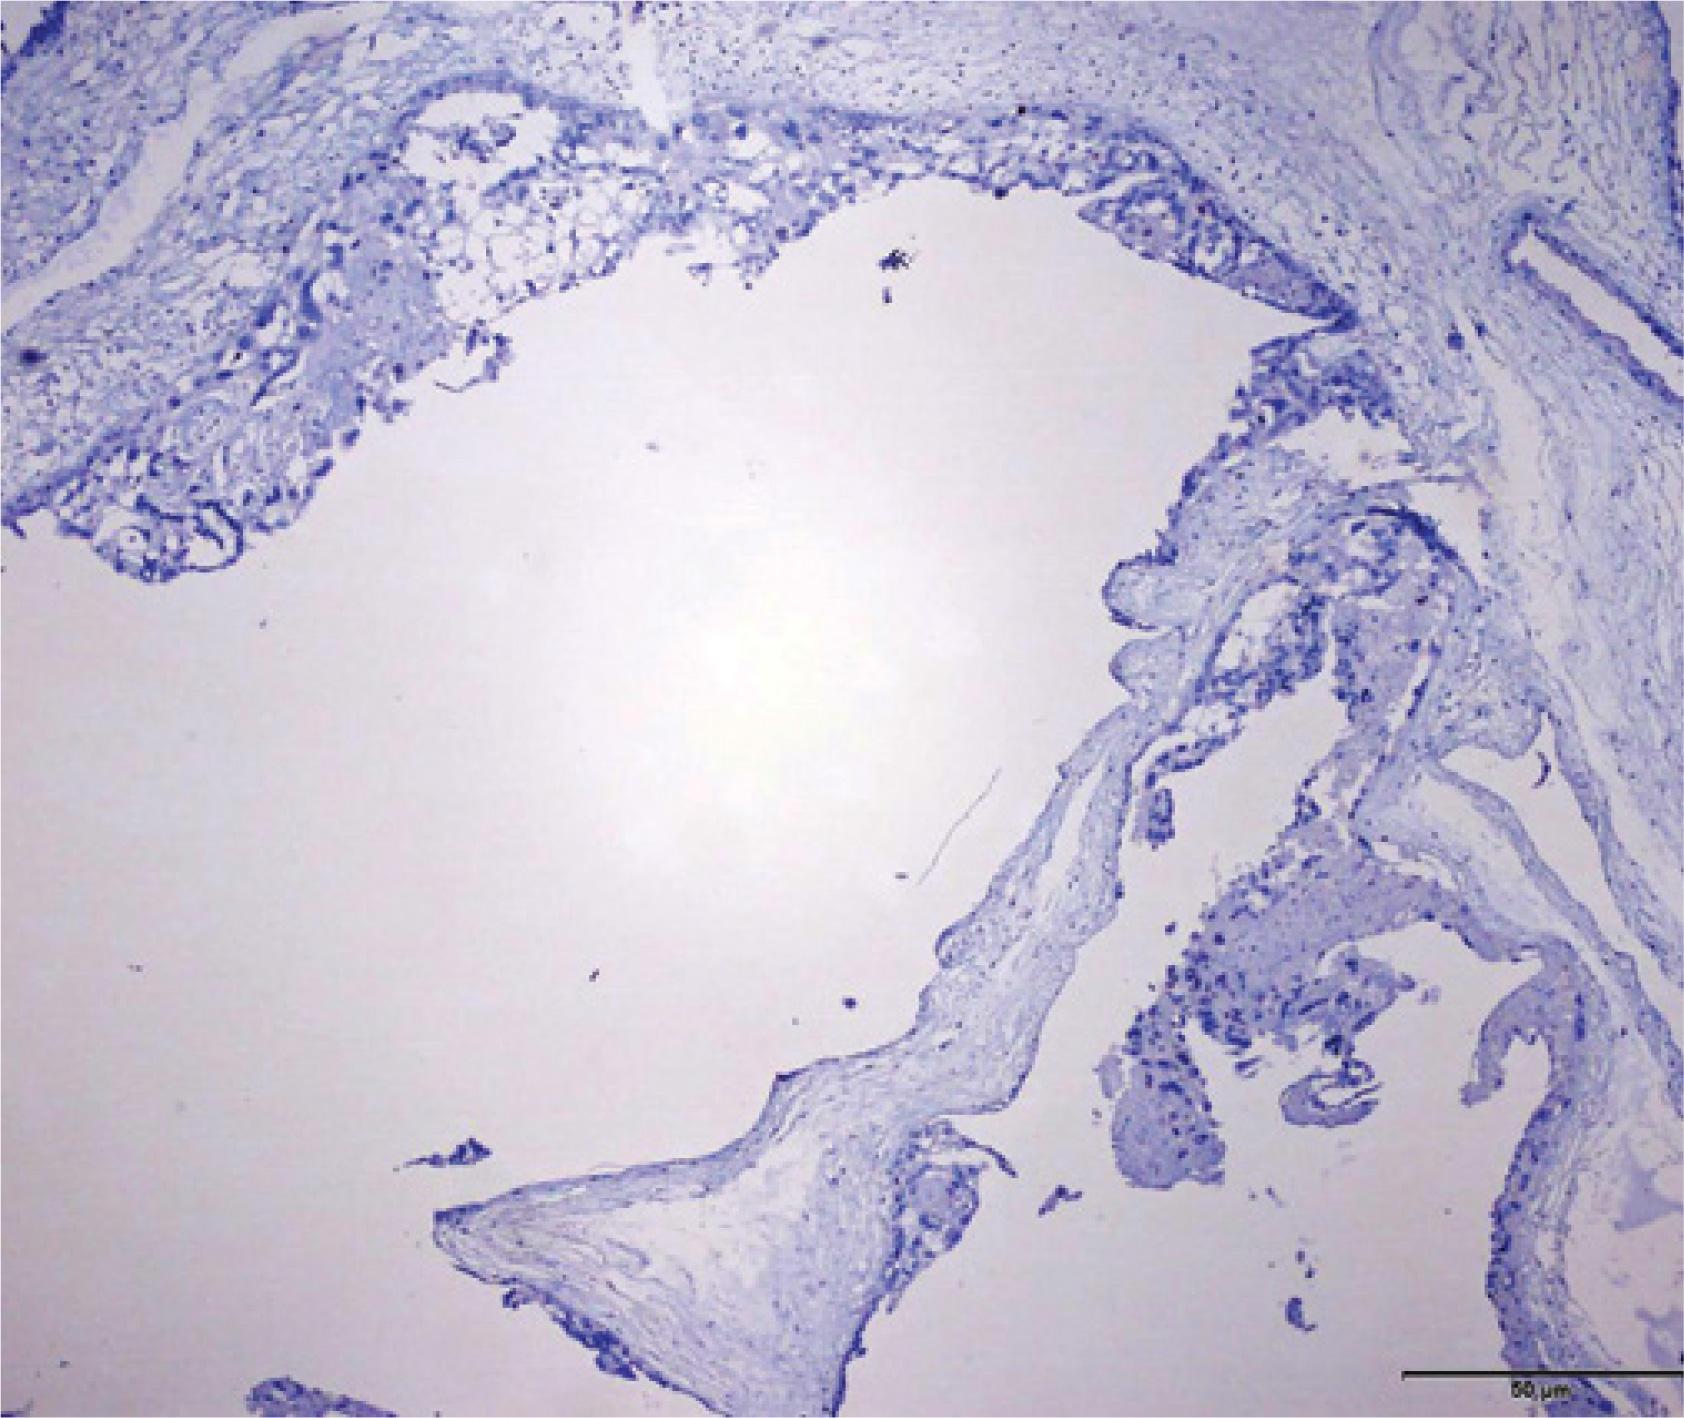

Fig. 4